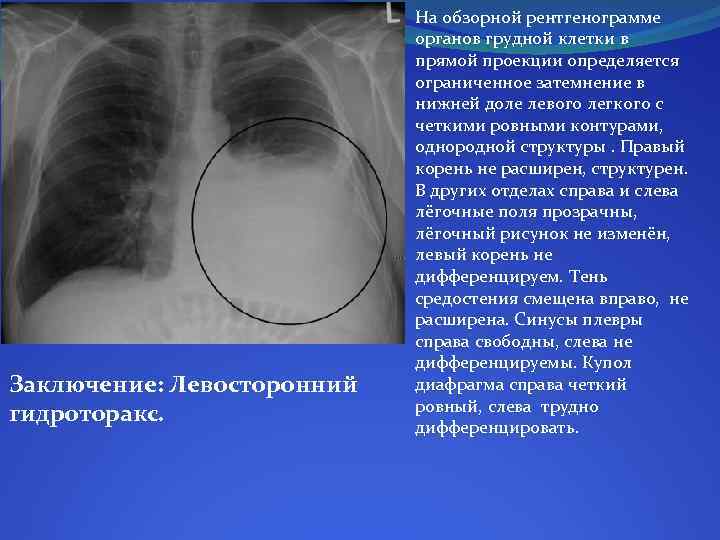

Дифференциальная диагностика заболеваний плевры